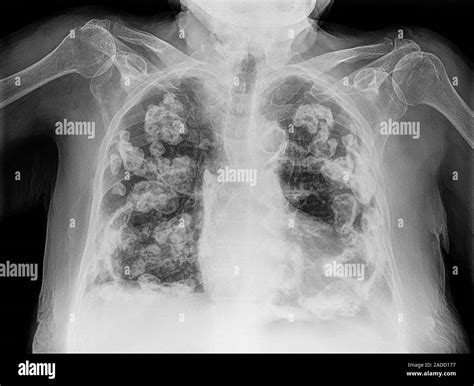

• Chest X-ray: A chest X-ray can reveal the presence of calcium deposits in the lungs.

• CT Scan: A computed tomography (CT) scan provides detailed images of the lungs and can help identify the location and extent of the calcification.